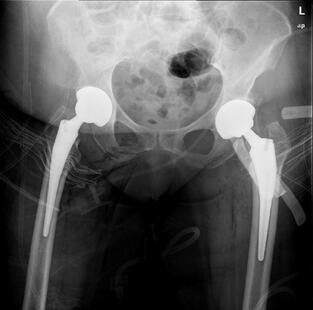

Τα περισσότερα εμφυτεύματα σήμερα έχουν παρόμοια σχέδια και σχήματα, αλλά ο γιατρός σας θα καθορίσει ποια σχέδια λειτουργούν καλύτερα για το σώμα σας. Αυτά τα εμφυτεύματα είναι κατασκευασμένα από κοβάλτιο χρώμιο ή τιτάνιο. Μια μεταβλητή που παραμένει ακόμα είναι η επιφάνεια φόρτισης. Η επιφάνεια φόρτισης είναι η σφαίρα, η κεφαλή και η επένδυση που προσκολλώνται στο μηριαίο στέλεχος, και το κυπέλιο, η το κοτυλιαίο εμφύτευμα που στερεώνεται στο οστό. Η κεφαλή μπορεί να αποτελείται είτε από μέταλλο (κράμα χρωμίου κοβαλτίου) είτε από κεραμικό και η επένδυση μπορεί να είναι από πλαστικό (πολυαιθυλένιο), μέταλλο ή κεραμικό. Η κεφαλή και η επένδυση μπορούν στη συνέχεια να χρησιμοποιηθούν σε διαφορετικούς συνδυασμούς και ονομάζονται για τον αντίστοιχο συνδυασμό επένδυσης κεφαλή (μέταλλο σε πολυ, κεραμικό σε πολυ, κεραμικό σε κεραμικό κ.λπ.).

Το 2023, τα περισσότερα χρησιμοποιούσαν επένδυση πολυαιθυλενίου με κεραμική κεφαλή, ενώ άλλοι συνδυασμοί χρησιμοποιούνται με μικρότερη συχνότητα. Μπορείτε να συζητήσετε αυτές τις διαφορές με τον χειρουργό σας για να προσδιορίσετε ποιο εμφύτευμα είναι καλύτερο για εσάς.